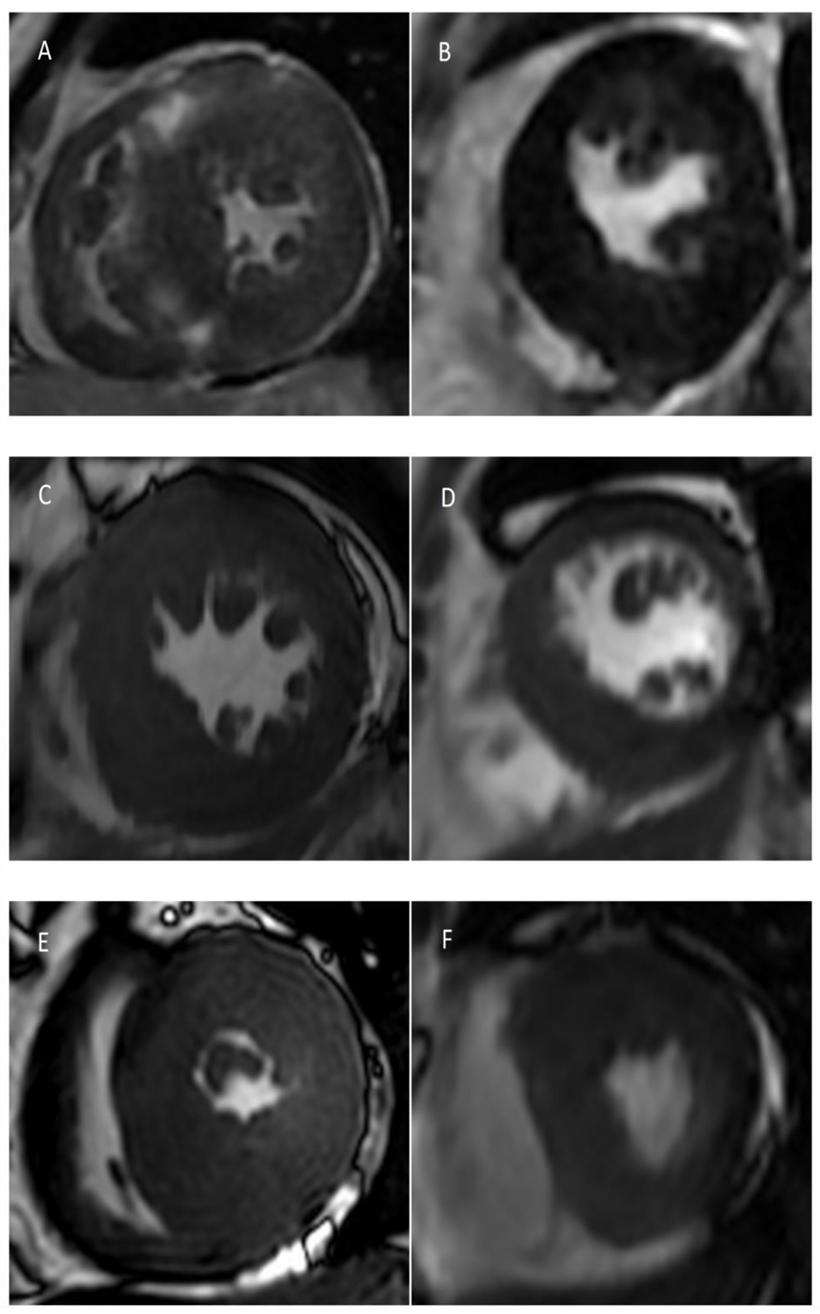

2.2. CMR Image Acquisition

2.3. CMR Image Analysis